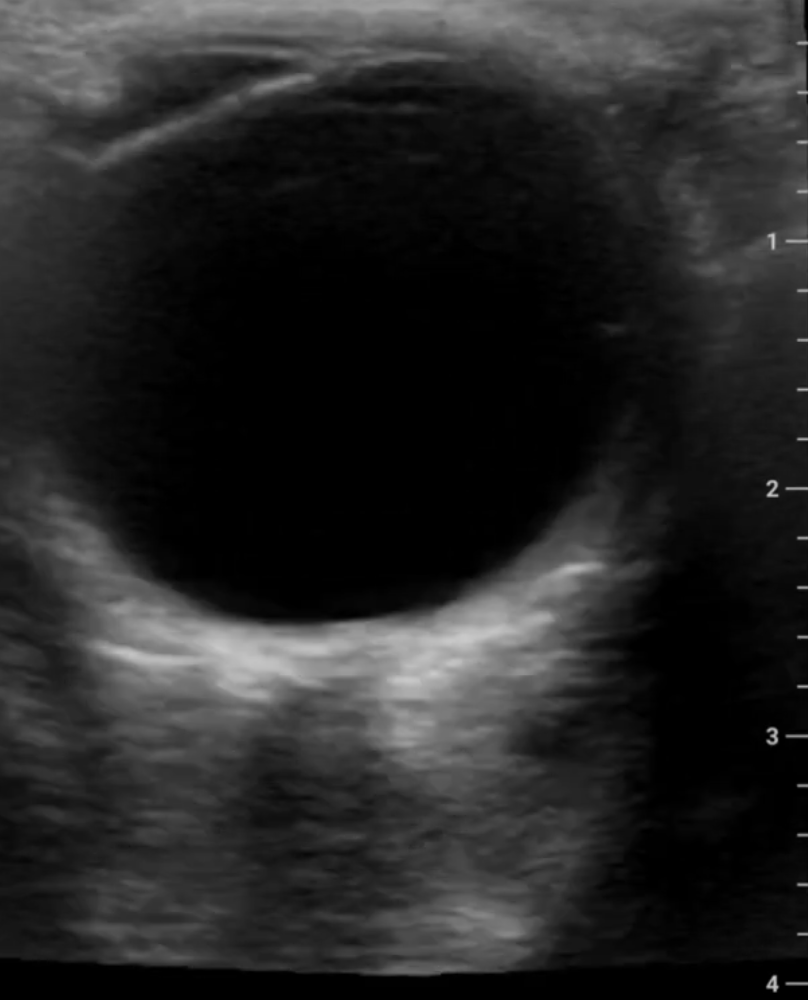

Ultrasound Images

This model of my eye was created using images captured by the device.